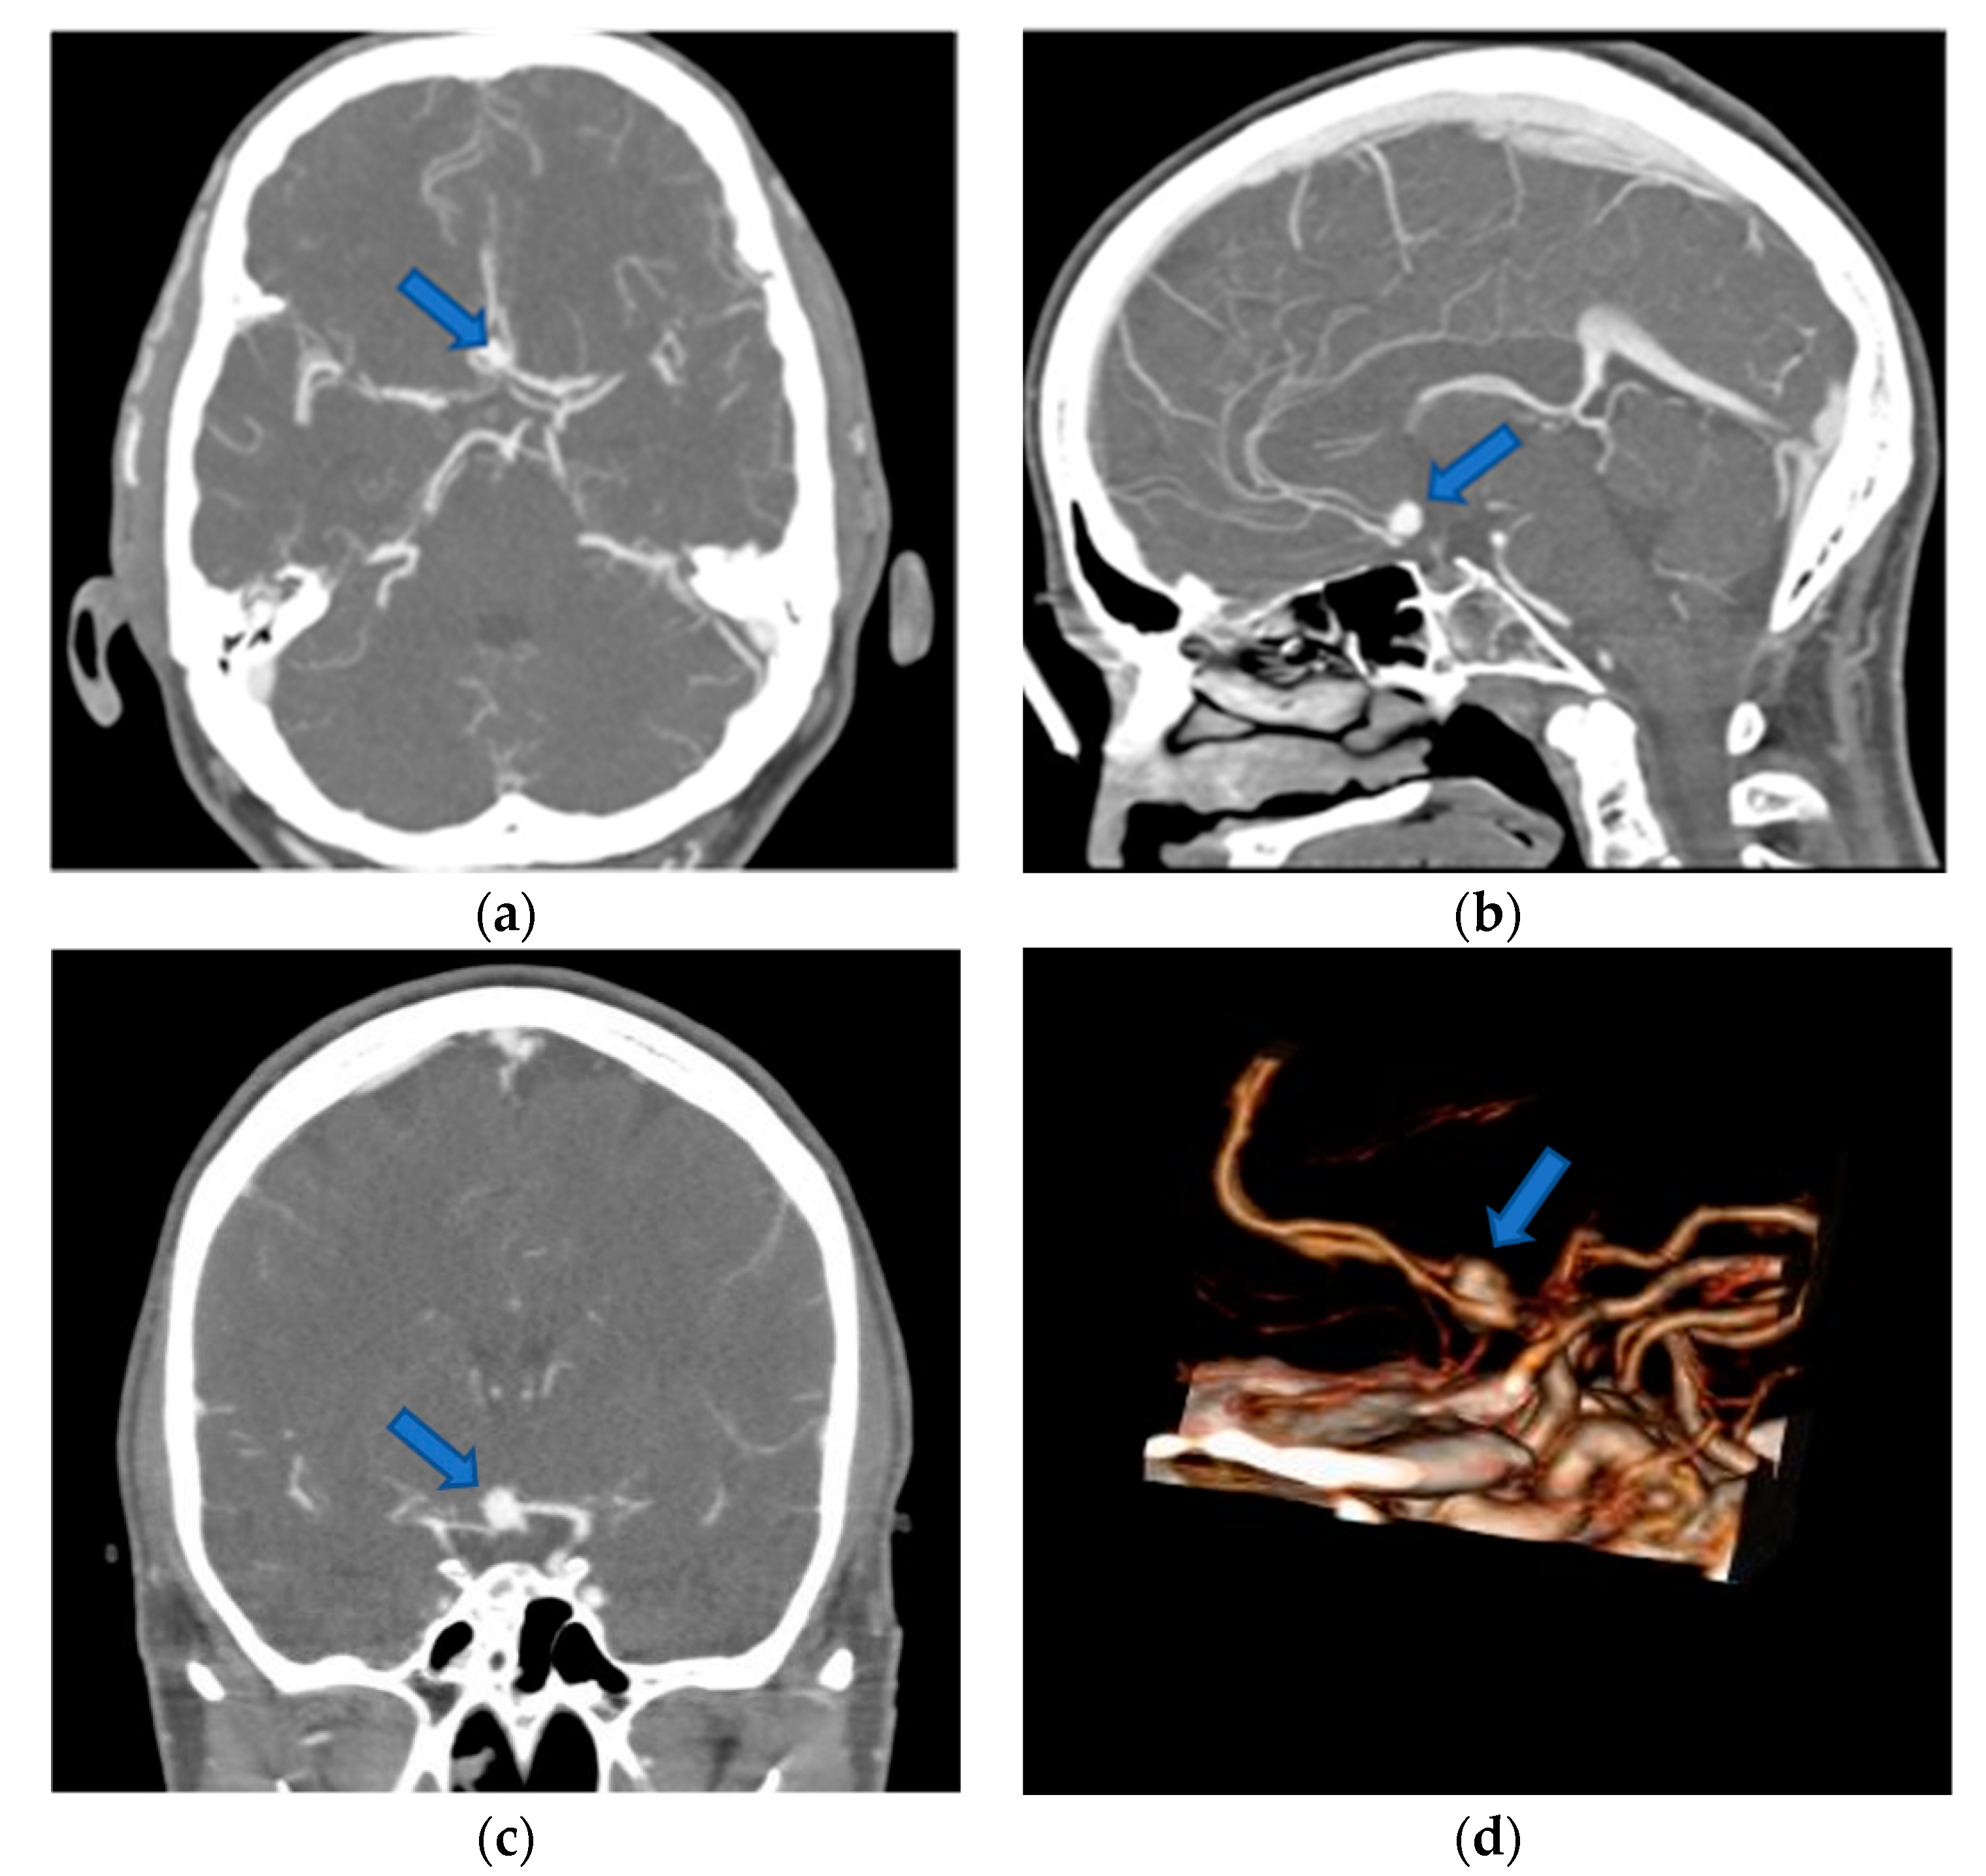

Conventional preoperative screen CTA scans (examples in Figure 2) of all included patients were retrospectively demonstrated to ten experienced, board-certified neurosurgeons who have at least 10-years-experience in vascular neurosurgery with at least 50 aneurysm clippings performed by each of them (to reduce any influence on the recommendations given and to avoid bias, neurosurgeons who performed the operations and who have done the reconstructions were excluded). They were asked to evaluate the identification of anatomical structures, as well as determine the preferred patient and head positioning, the surgical approach and approach side, and the clipping strategy using a questionnaire (Table 1). The reconstructed 3D-VR images (examples in Figure 3) of the same patients were retrospectively presented to the same neurosurgeons four weeks later, but in a different order to minimize the influence from the first questionnaire on the second. Again, the neurosurgeons were asked via the same questionnaire. To avoid influence from the patient- and disease-related data on the image evaluations, these data were not presented. The possible influence of the preoperative reconstructed 3D-VR images compared to the conventional preoperative CTA scans (2D and screen 3D) on detection of anatomical structures and on surgical planning and strategy was evaluated.

Figure 2.

Preoperative 2D-CTA and screen 3D-CTA images of patients with unruptured ACoA aneurysm (blue arrows). (a) Axial 2D-CTA image presenting anteriorly directed ACoA aneurysm; (b) sagittal 2D-CTA image presenting superiorly directed ACoA aneurysm; (c) coronal 2D-CTA image presenting superiorly directed ACoA aneurysm; (d) lateral screen 3D-CTA image presenting anteriorly directed ACoA aneurysm. 2D, two-dimensional; 3D, three-dimensional; ACoA, anterior communicating artery; CTA, computed tomography angiography.